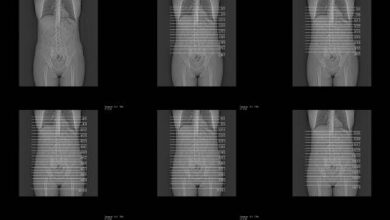

Overview Femoral hernias are relatively rare, accounting for only 3% of all hernias and approximately 6% of all groin hernias.…